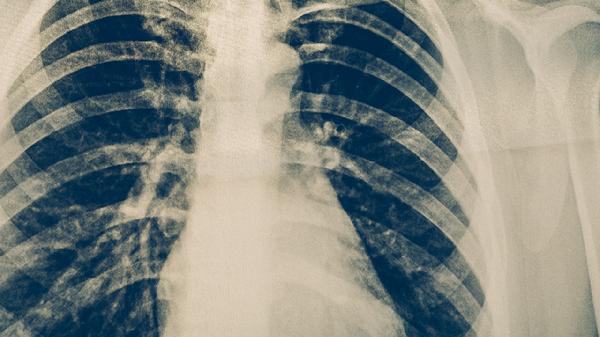

影像学检查是诊断原发性腹膜后肿瘤的重要手段,包括超声检查、CT检查、MRI检查等。超声检查操作简便且无辐射,可初步判断肿瘤位置和大小。CT检查能清晰显示肿瘤与周围组织的关系,评估是否有淋巴结转移。MRI检查对软组织分辨率高,有助于判断肿瘤性质和侵犯范围。